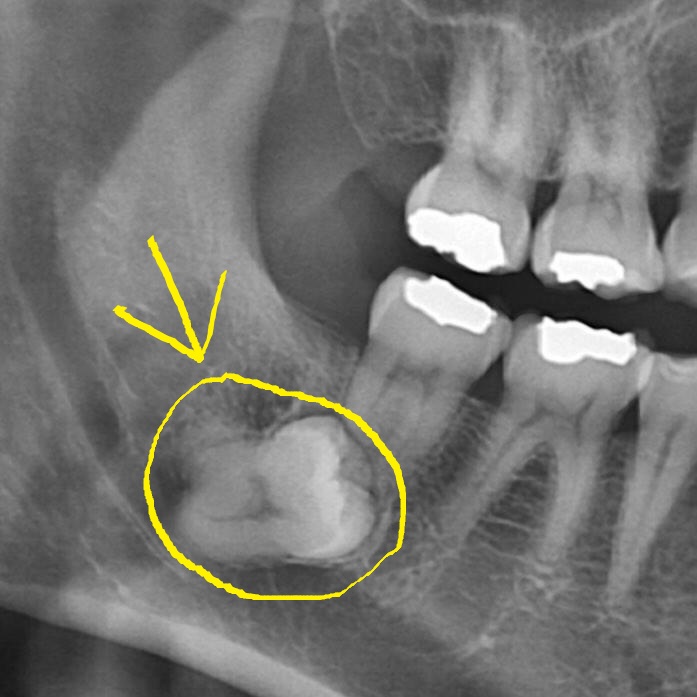

이 정도면 사랑니 발치 고난도라고 합니다. 문외한인 제가 봐도 왠지 움찔하게 되네요...;;